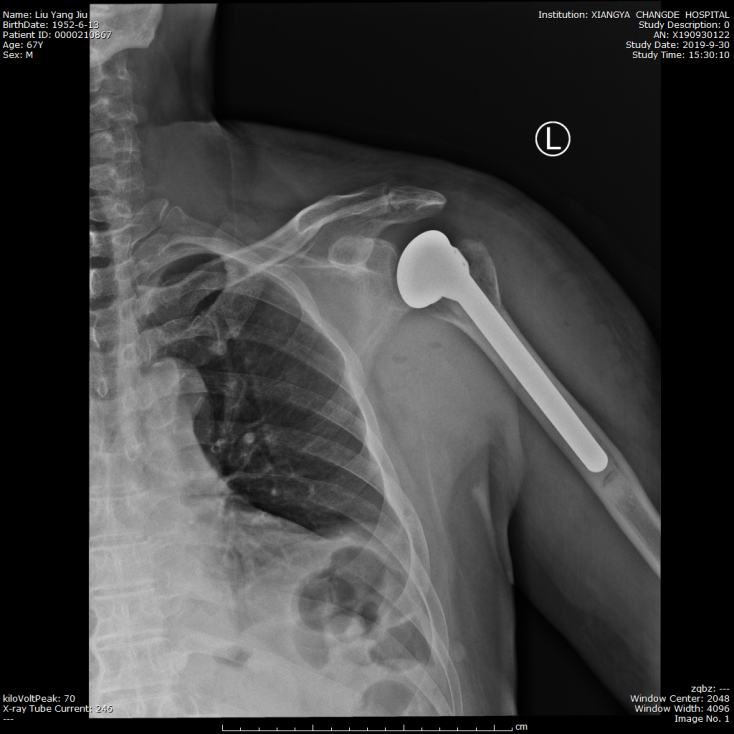

近日,湘雅常德医院骨科成功实施了首例人工肩关节肱骨头置换术,这标志着湘雅常德医院关节外科在关节置换领域达到又一新高度。   某日清晨,67岁的刘大爷驾驶摩托车不慎摔伤,自觉左肩关...